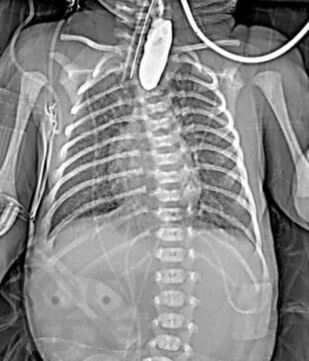

В пособии рассматриваются современные принципы диагностики и лечения хирургических заболеваний новорождённых и детей первого года жизни, возможных осложнений и исходов. Акцентируем внимание студентов на эмбриогенез, этиологию и патогенез, классификацию, клинические проявления и выбор методов лечения. Пособие содержит вопросы для самоконтроля и список литературы для дополнительного изучения.

Пособие подготовлено по дисциплине «Детские хирургические болезни» в соответствии с Федеральным государственным образовательным стандартом высшего профессионального образования для студентов V, VI курсов, обучающихся по основным образовательным программам - программам специалитета по специальности «Педиатрия» и для студентов, обучающихся по основным образовательным программам - программам специалитета по специальности «Лечебное дело».